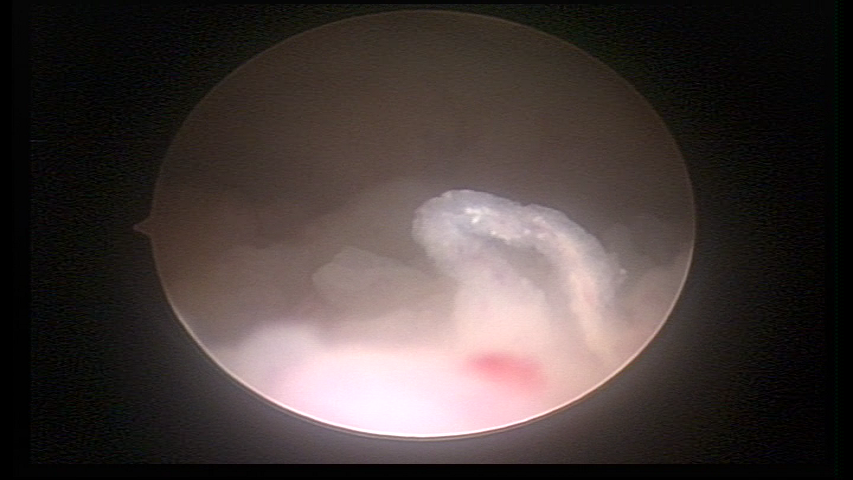

Este pode apresentar uma gama variável de aspectos macroscópicos, com aspecto pseudopolipoide; lembrando tecido cerebroide ou com reação deciduoide; a vascularização superficial é mais evidente e com vasos em formatos de saca-rolha ou espirais visualizando também a vascularização com atipias, com aumento do calibre dos vasos superficiais, pode ser encontrado também tecido em necrose, poderá haver pequenos dendritos (papilomatoso).